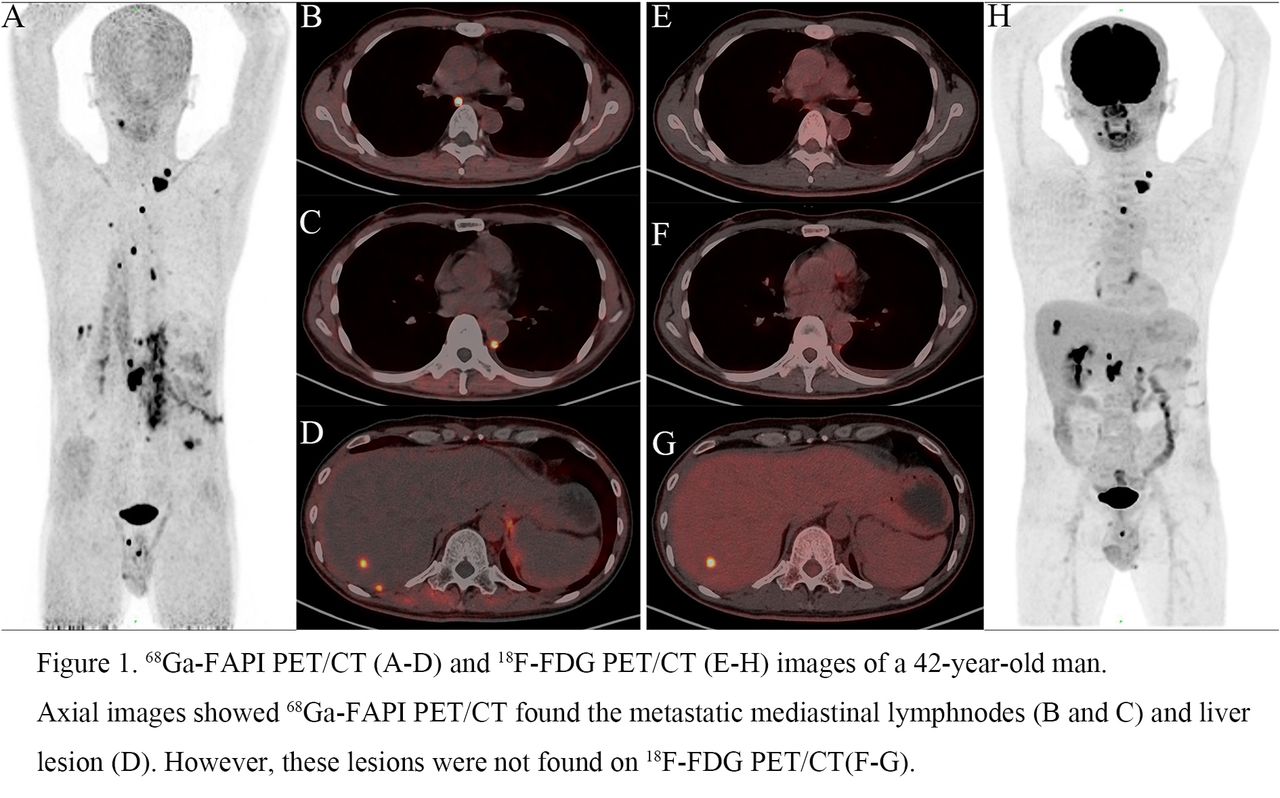

![Value of [68Ga]Ga-NYM046 PET/CT, in Comparison with 18F-FDG PET/CT, for ...](https://jnm.snmjournals.org/content/jnumed/65/12/1884/F6.large.jpg)